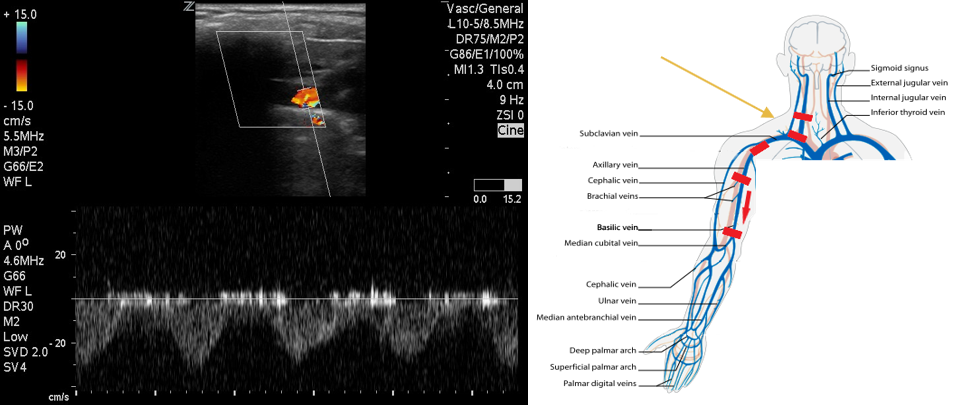

- Follow the IJ to the confluence with the SCV where they form the brachiocephalic vein. Compression in this region will not be possible. Use color flow to evaluate for filling defects and pulsed wave Doppler to evaluate for flow patterns. Absent or monophasic patterns are abnormal. Biphasic or triphasic flow is normal.

- Figure 4. Pulsed wave Doppler over subclavian vein demonstrates biphasic flow.